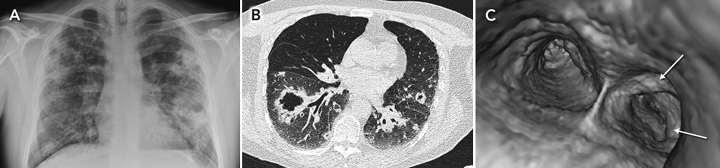

Pulmonary amyloidosis occurs in three forms: tracheobronchial (the most common, which is limited to central airways and which this case exemplifies), diffuse and adenopathy-associated.1 Nearly all cases are of the light-chain type.2 Treatment is difficult and controversial; repeated bronchoscopic resection is conventional,3 but the role of external beam radiotherapy in tracheobronchial amyloidosis has also been described.4